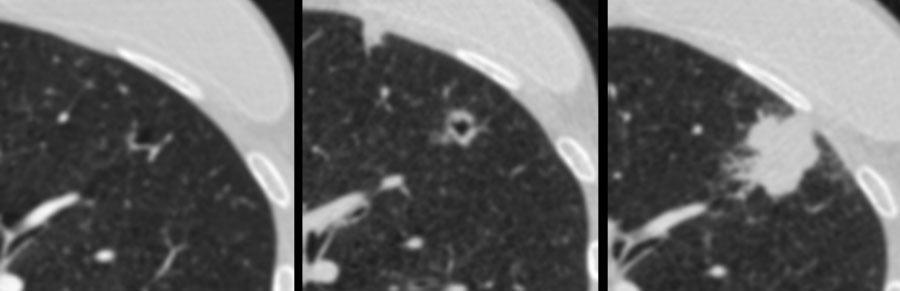

Các hình ảnh minh họa một ví dụ khác về ung thư phổi dạng nang biểu hiện quá trình ‘đặc hóa’.

Đây là một ví dụ khác về ung thư phổi dạng nang biểu hiện quá trình ‘đặc hóa’, từ tổn thương tiền thân ban đầu với dày thành không đều kín đáo tiến triển thành một khối đặc tại thời điểm chẩn đoán.